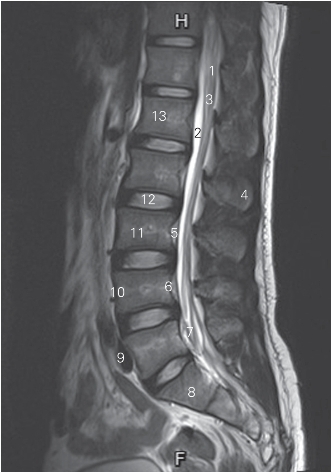

图3-12 经脊柱腰、骶尾段正中矢状断层MR T2加权图像

1 脊髓 spinal cord 2 终池 cisterna terminalis

3 脊髓圆锥 conus medullaris 4 棘突 spinous process

5 后纵韧带 posterior longitudinal ligament

6 椎基底静脉 vertebral basilar vein

7 终丝和马尾 filum terminal and cauda equina

8 第1骶椎椎体 1st sacral vertebrae 9 髂总动脉 common iliac artery

10 前纵韧带 anterior longitudinal ligament

11 第3腰椎椎体 3rd lumbar vertebral body

12 第2腰椎间盘 2nd lumbar intervertebral disc

13 第1腰椎椎体 1th lumbar vertebral body